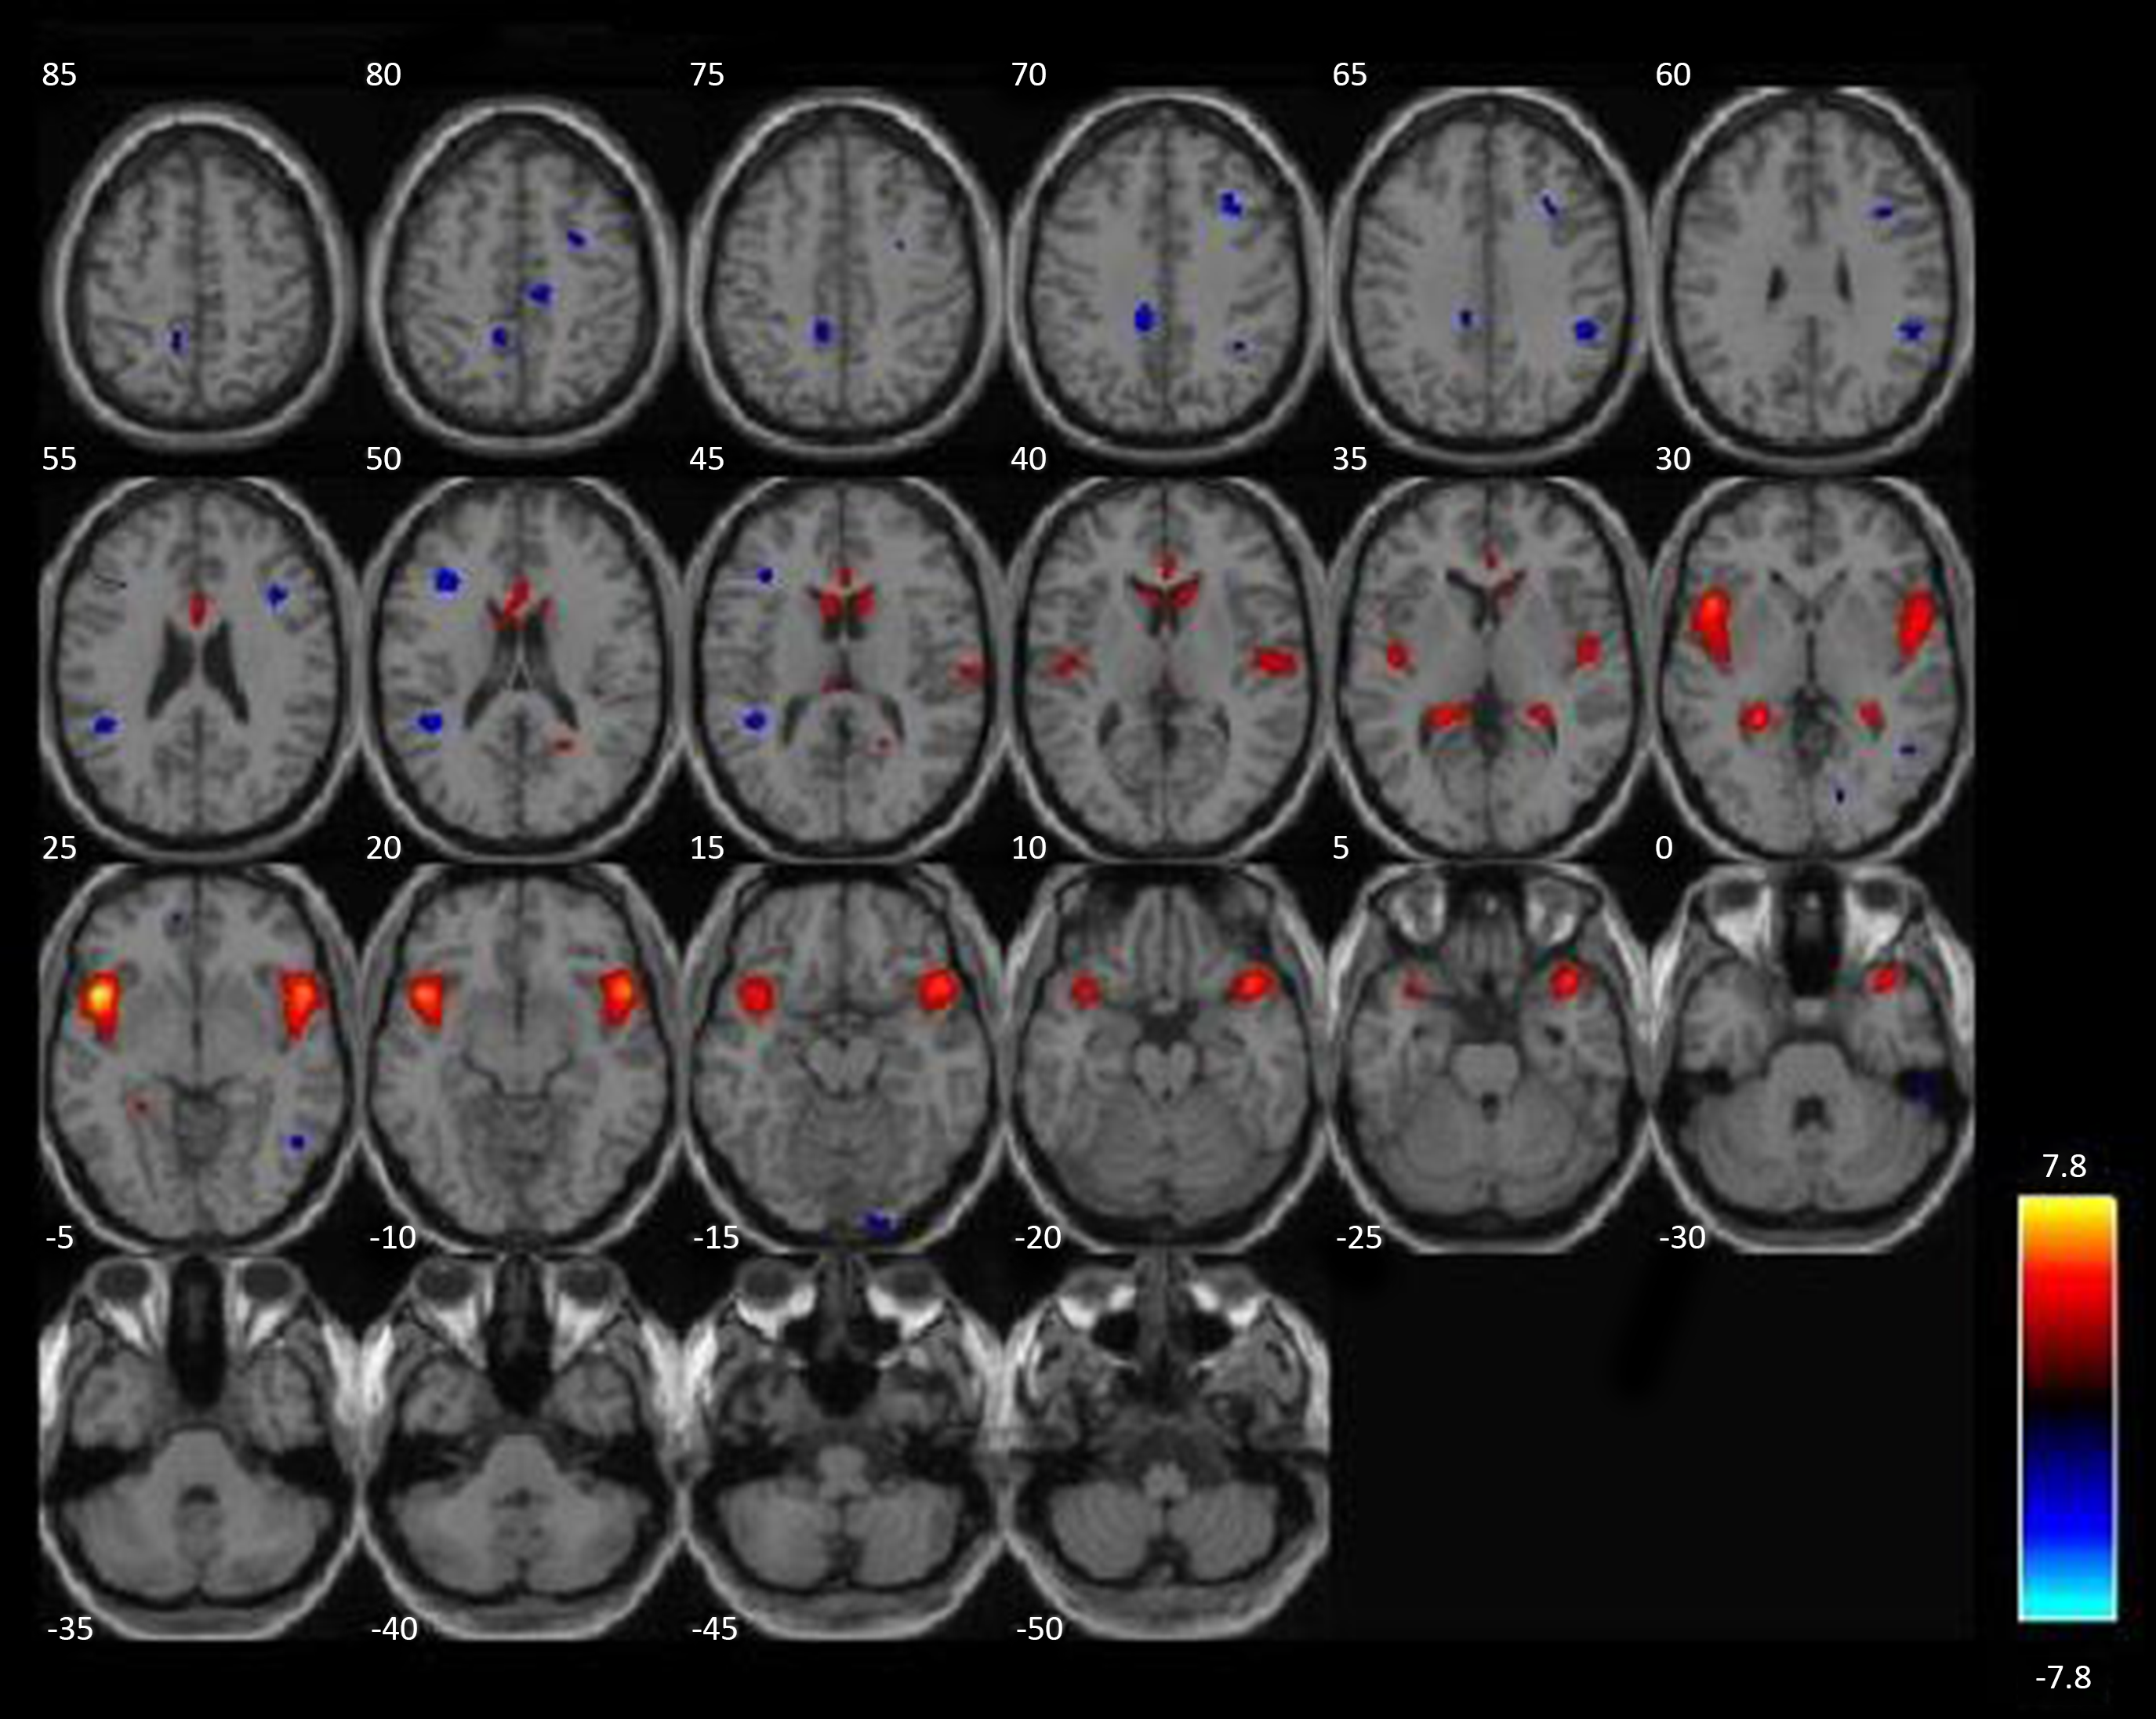

Two structural networks (derived by ICA) exhibited more than 10% overlap with a priori ROIs, together accounting for 80% of voxels examined in the GLM analysis. A network including bilateral striatum was positively correlated with substance use severity using bivariate correlations, r = .213, p = .008 (see Fig. 2). A second structural network including bilateral insula was also positively correlated with substance use severity, r = .166, p = .04 (see Fig. 3). After controlling for other covariates (age, race, IQ, PCL:YV, GM + WM), the striatal component remained significant (partial r = .194, p = .018), but the insular component only trended in the same direction (partial r = .137, p = .096). Three additional components (out of 28 remaining), which did not include a priori regions of interest, also exhibited potentially meaningful relationships with substance use severity. These components included structural networks comprising the posterior cingulate and precuneus (both positively correlated with substance use), and a network including the posterior cerebellum was significantly negatively correlated with substance use severity. These incidental findings are presented for completeness in the supplementary materials; however, these effects do not survive corrections for multiple comparisons if evaluated from an agnostic, whole-brain approach. Nevertheless, they may be of interest in the context of developing new hypotheses for future investigations.

Figure 2. An intrinsic network with elevated gray matter in those with more severe substance use. A structural network, derived from ICA, n = 152, positively correlated with substance use severity is highlighted in red/orange. More severe substance use is associated with proportionally more gray matter throughout this intrinsic network, which includes caudate, putamen, nucleus accumbens, ventromedial PFC, and parts of the anterior insula (a priori ROIs). ICA = independent component analysis.

Figure 3. A second intrinsic network with increased gray matter associated with more severe substance use. A second structural network, derived from ICA, n = 152, positively correlated with substance use severity, highlighted in red/orange. More severe substance use is associated with proportionally more gray matter throughout this intrinsic network, which includes bilateral insula (a priori ROIs). ICA = independent component analysis.